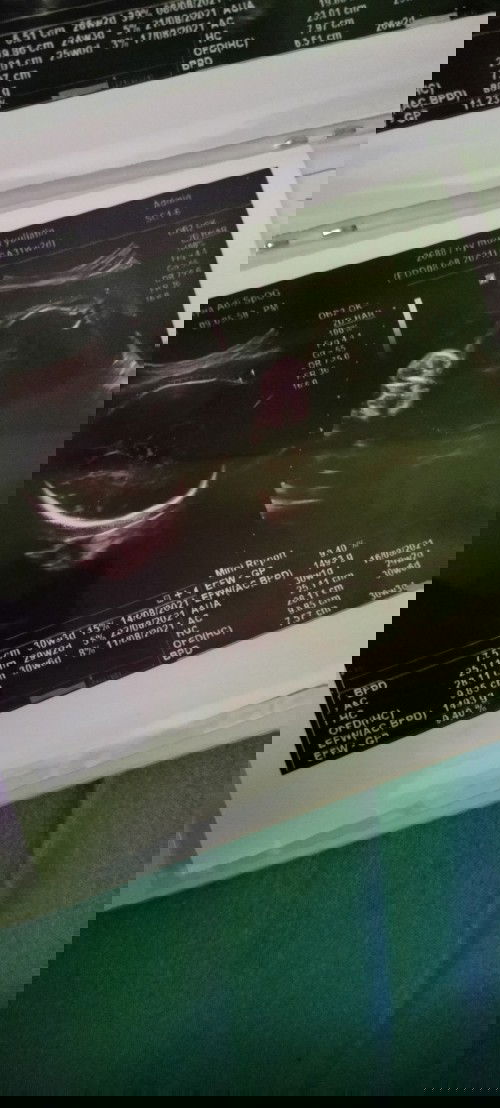

Hpl agustus awal... Ap ad yg wktu usg babynya kelilit tali pusar.... Apkah masih bisa berubah..

aku hpl bln september, tgl 6 kemaren aku usg sempet kaget, janin kelilit tali pusar, tapi ke mungkinan bakalan bisa berubah, saking aktifnya baby, tgl 20 suruh balik cek usg untuk memastikan